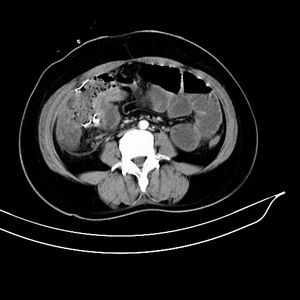

女 42岁 子宫肌瘤于外院术后两天,感腹胀。x线提示肠梗阻。

子宫肌瘤于外院术后两天,出现肠扭转梗阻,很明显。但右下腹部出现的线状高密度,是什么呢?有什么手术会有这样的物品呢?不会把电刀的导线遗留在腹腔吧!?

结果:术后纱布遗留,术后麻痹性肠梗阻肠梗阻

上面的图像是我们从手术室拿来的纱布做了个ct平扫,发现纱布里确实存在有一条致密影。后得知致密影是为防止手术时纱布遗留而设计。关腹时怀疑纱布遗留可做个床边透视或拍片可明确。